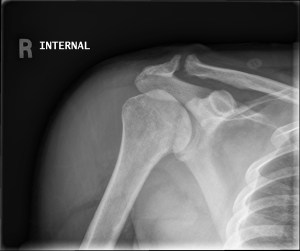

History: 40 year old patient with spinal cord injury.

This is a case of neuropathic osteoarthropathy, also known as a Charcot joint. The imaging findings are typically described as the 5 “Ds,” which include normal bone Density, joint Distension, bony Debris, cartilage Destruction, and joint Disorganization (or dislocation/deformity). Usually when seen in the shoulder it is indicative of an entity called syringomyelia, however, in this patient it was spinal cord injury.